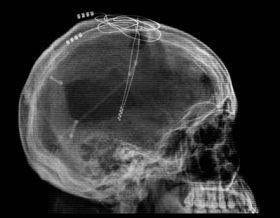

Применение магнитной стимуляции, как и транскраниальная стимуляция постоянным током (tDCS), представляют собой неинвазивные методы воздействия, которые помимо очевидных достоинств имеют один недостаток. Вследствие того, что источник поля располагается на поверхности черепа, затронутым оказывается лишь небольшой слой коры, дальше которого стимуляция не оказывает никакого влияния. Однако в мозгу существуют структуры, находящиеся достаточно глубоко, и подача электрического тока на них также приводит к удивительным и благотворным для человека результатам. Чтобы добраться до этих структур, ученые используют метод глубокого вживления электродов в ткань мозга.

Как позже показали томографические исследования, некоторые важные участки коры остались нетронутыми, но не функционировали. Это обстоятельство заинтересовало ученых. Они предположили, что в результате травм был отключен механизм, активирующий кору. Ключевая роль здесь принадлежит таламусу — структуре, в которой происходит обработка и интеграция практически всех сигналов, идущих в кору большого мозга от спинного, среднего мозга, мозжечка и базальных ганглиев. По мысли медиков, если подвергнуть электростимуляции ядра таламуса, это может привести к пробуждению сохраненных участков коры. Однако таламус находится глубоко в мозгу, поэтому никакая неинвазивная техника до него не достанет. Единственная возможность — внедрить электроды хирургическим путем.

После долгих обсуждений, касающихся в основном этических коллизий, возникших в связи с оперированием человека без его согласия, процедура была исполнена. Практически сразу же, в первые два дня работы электродов, состояние пациента заметно улучшилось. Он стал держать глаза открытыми продолжительное время и отзываться на голоса, поворачивая голову. Ученые, однако, были вынуждены сделать паузу на 50 дней, чтобы удостовериться, что улучшение не является неизвестным эффектом хирургического вмешательства. Затем на протяжении 18 недель таламус стимулировали различными сочетаниями частоты и продолжительности возбуждений, дабы найти наилучший вариант.